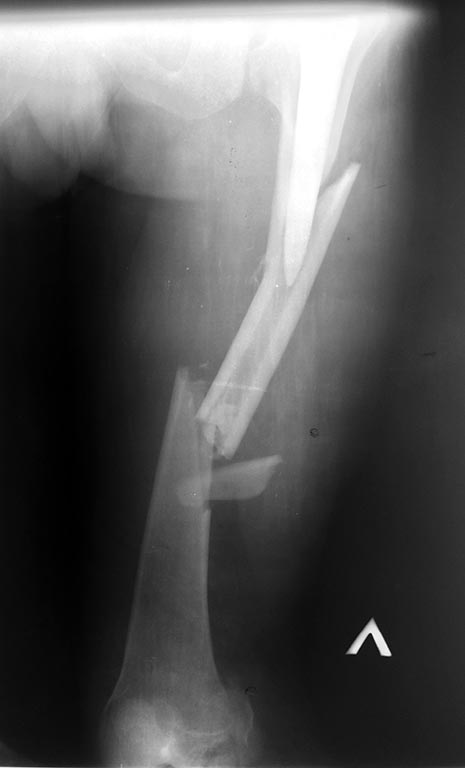

Перипротезный перелом бедра и перелом костей голени

Здравствуйте!Пациент М 54 года. 25.05.2015 г. в результате ДТП получает сочетанную травму.

Снимки прилагаются. Интересно ваше мнение по тактике лечения данного пациента. Есть многочисленные металлоконструкции и технологии оперативных вмешательств.

P.s. Прошу прощение за качество снимков.